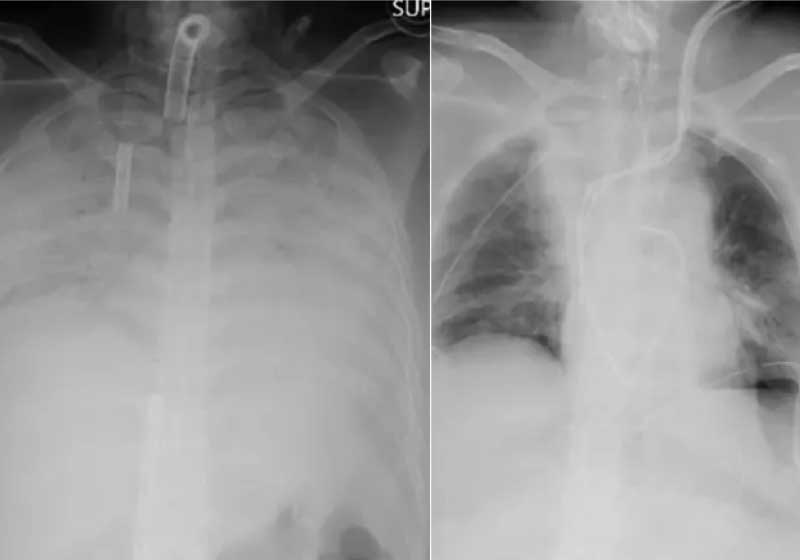

As complicações levaram a paciente a ficar por meses em uma máquina que funcionava como um pulmão artificial, de acordo com o Hospital da Universidade de Kyoto.

A covid deixou sequelas fortes no pulmão da mulher, a ponto de o órgão não funcionar mais sem apoio de um aparelho.

Com a necessidade de transplante, veio também a necessidade de um doador compatível. Só que o marido e o filho da mulher se ofereceram para doar partes de seus pulmões e o hospital começou a pensar a respeito.